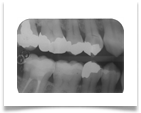

Nel nostro Studio impieghiamo un sistema radiografico computerizzato, il Vista Scan Plus della Dürr che consente di ottenere immagini di alta qualità (vedi confronto analogico/digitale) con dosi radiogene sensibilmente più basse per il paziente.

Con Vistascan Plus siamo in grado di ottenere, nel giro di pochi minuti, tutte le immagini che ci servono per un corretto ausilio diagnostico: bitewing, endorali, ortopantomografie, teleradiografie.